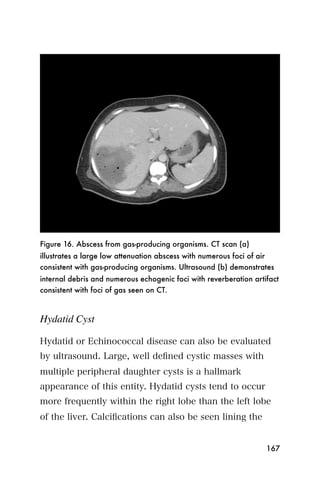

!"#$#%&"'#(%)*+,+-%.$&%--+/0&

&2345<2$&424$,.       .2657=$>?537$,.

0767$89:4;26$,.      &23456$&424$,.       %;5=@$A?B7$,.